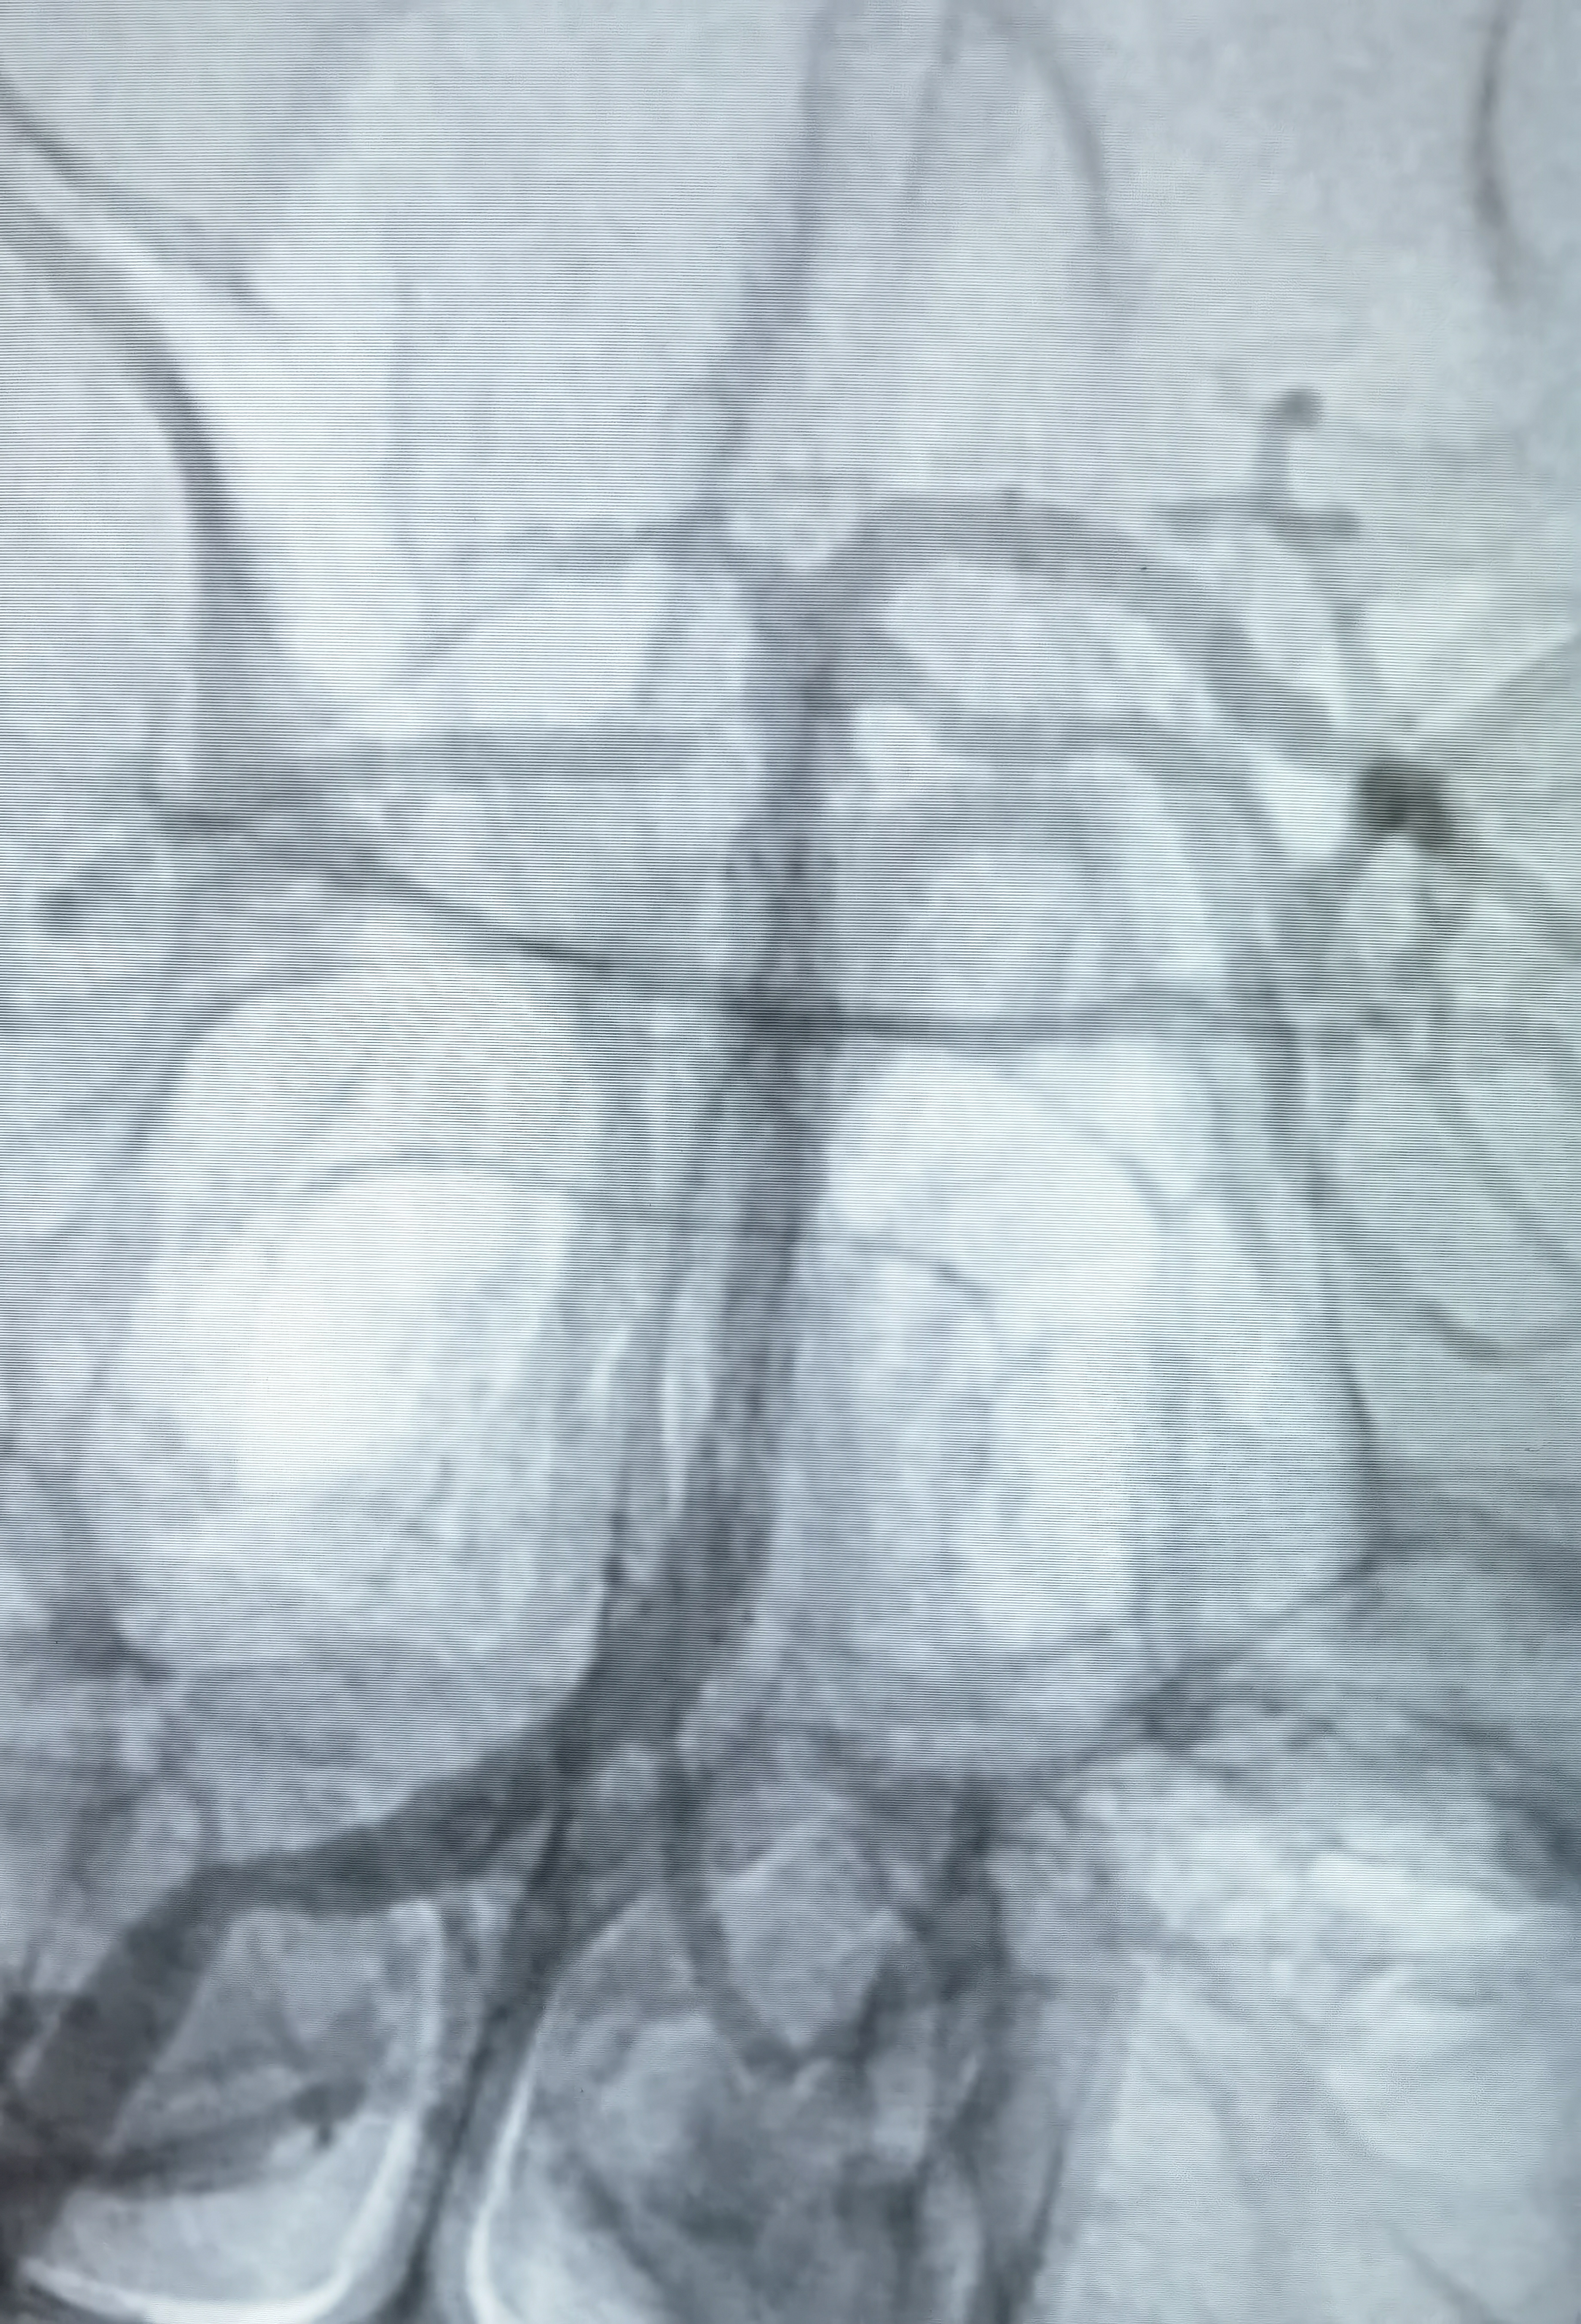

狭窄85%

Gateway2.5*15压力打至8atm